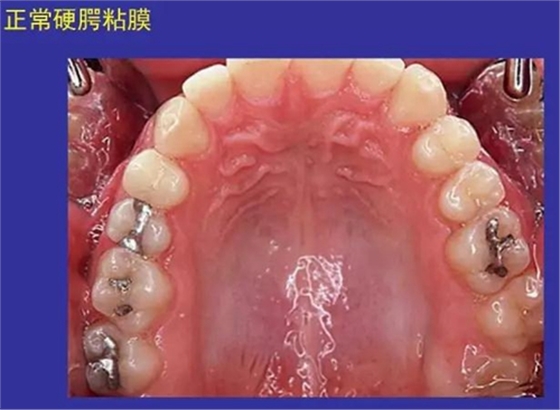

一、正??谇火つD

正??谇火つぜ俺R姴p圖